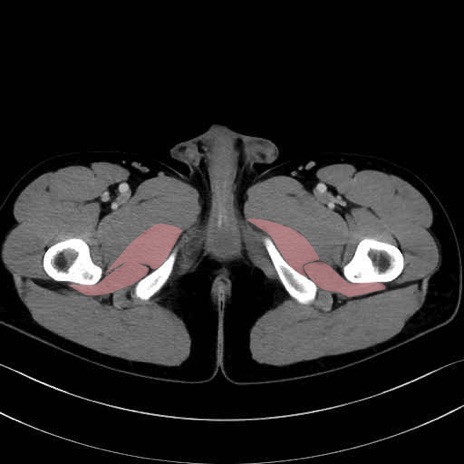

大内転筋(Adductor magnus)、小内転筋(Adductor minimus) のCT画像の解剖

大内転筋・小内転筋 (Adductor magnus / Adductor minimus)